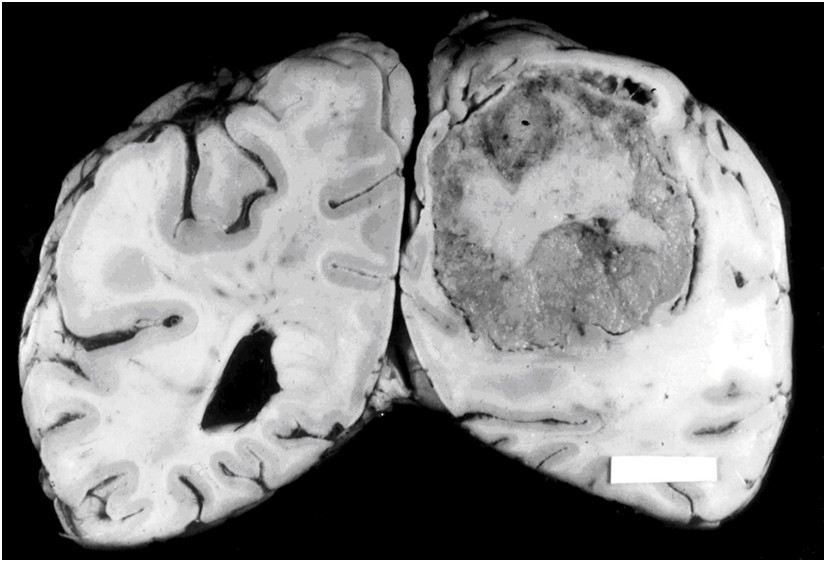

W nowotworach układu nerwowego, rozrost naczyń krwionośnych przybierający postać ogniskowych zagęszczeń, często tworzących kłębki naczyniowe może świadczyć o: